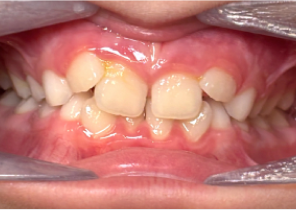

Báo cáo ca 2

7 tuổi 11 tháng, 24 bước nong của Nong hàm khẩu cái Invisalign®

Hàm được nong sau khi sử dụng nong hàm khẩu cái Invisalign®

Sau khi điều trị với Nong hàm khẩu cái Invisalign